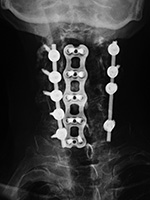

| Anterior cervical fusion plate |

Anterior Cervical Diskectomy and Fusion (ACDF) plate |

Cervical spine fusion cage and anterior cervical fixation plate |

| 53 year-old man with disk herniation. Anterior cervical fusion plate spans C3 to C6. |